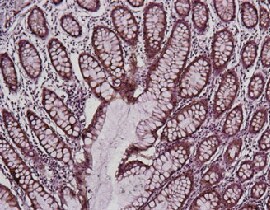

福尔马林固定石蜡包埋 (FFPE) 扁桃体组织的免疫组织化学分析。使用SuperBoost (A) EverRed & (B) EverBlue染色或(C) DAB染色分析人扁桃体组织FFPE切片。为了暴露靶蛋白,使用 10 mM 柠檬酸钠 (pH 6.0) 进行热诱导抗原修复 (HIER) ,然后在压力锅中加热 20 分钟。HIER 后,将组织在室温下 3% H2O2 孵育 10 分钟,用封闭试剂封闭,然后在 4°C 下用 Invitrogen Ki-67 单克隆抗体 (货号号 MA5-14520) ,以 PBS/3% (w/v) BSA 中按 1 : 20 稀释。样本广泛溶于含 0.05% (v/v) 吐温 -20 (PBST) 的 PBS 缓冲液中洗涤。使用 SuperBoost (A) EverRed 山羊抗兔 IgG (货号 A) 进行检测号 E40967) , (B) EverBlue 山羊抗兔 IgG (货号号 E40968) ,或 (C) DAB ,使用 SuperBoost 山羊抗兔 Poly HRP IgG (货号号 B40962)。封片前用乙醇和二甲苯脱水。使用EVOS M7000成像系统(货号 AMF7000) , 4 x物镜采集。